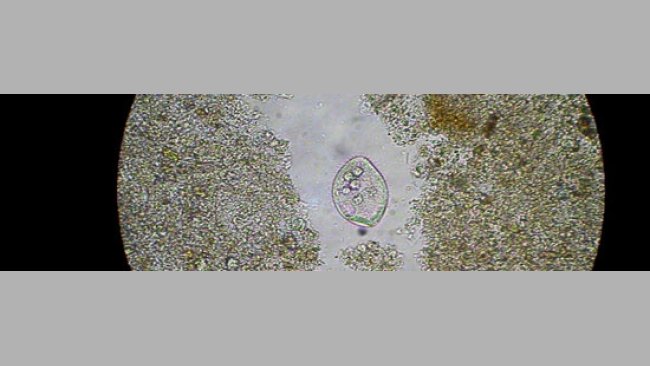

Para explicar parte de la diarrea post-destete se ha estudiado el desarrollo del sistema inmunitario intestinal.